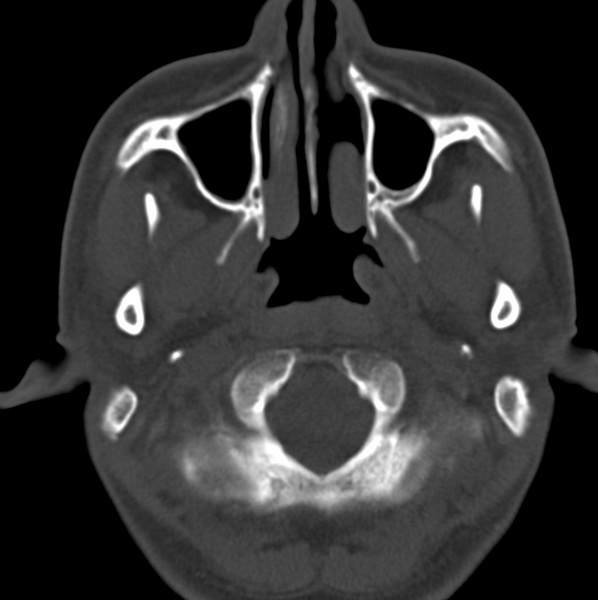

男、31、鼻咽部肿瘤放疗后请帮忙看看。

效果好,右侧破裂孔扩大,局部骨质缺损,为颅底骨质破坏。

1)鼻咽部肿瘤侵犯颅底放疗术后改变。2)左侧蝶窦炎。

咽后壁增厚,左侧咽鼓管隆突增大、咽鼓管咽口变浅,同侧咽旁间隙较窄。右侧颅底骨质破坏?为什么不在同一侧?

鼻咽部肿瘤侵犯颅底放疗术后改变.